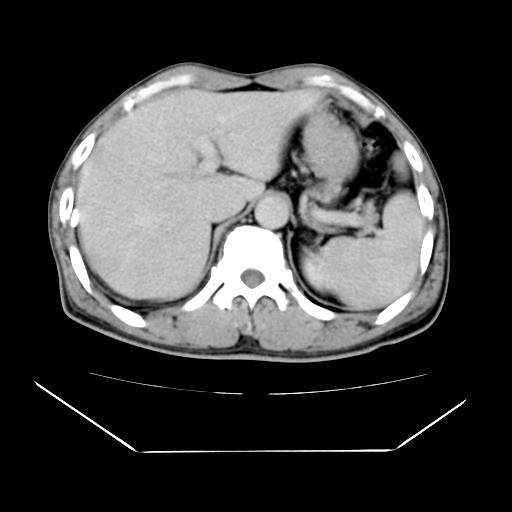

男性,55岁,外院体检afp明显升高,但b超未发现异常,否认乙肝病史。来我院ct增强。有延时扫描。

肝脏右叶动脉期可见低密度影,至延迟期被充填,考虑血管瘤可能性大。

肝右叶病灶

不排除肝右叶肝癌可能。

这个不是肝右静脉吗,这么大的病灶b超不可能发现不了吧

如果这个是癌灶的话则下腔静脉有瘤栓可能

肝6段血管瘤

血管瘤可能性大。

是肝右静脉吧

考虑肝右静脉影。